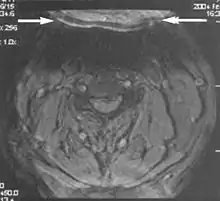

A motion artifact is one of the most common artifacts in MR imaging.[2] Motion can cause either ghost images or diffuse image noise in the phase-encoding direction. The reason for mainly affecting data sampling in the phase-encoding direction is the significant difference in the time of acquisition in the frequency- and phase-encoding directions.[1] Frequency-encoding sampling in all the rows of the matrix (128, 256 or 512) takes place during a single echo (milliseconds). Phase-encoded sampling takes several seconds, or even minutes, owing to the collection of all the k-space lines to enable Fourier analysis. Major physiological movements are of millisecond to seconds duration and thus too slow to affect frequency-encoded sampling, but they have a pronounced effect in the phase-encoding direction. Periodic movements such as cardiac movement and blood vessel or CSF pulsation cause ghost images, while non-periodic movement causes diffuse image noise (Fig. 1). Ghost image intensity increases with amplitude of movement and the signal intensity from the moving tissue. Several methods can be used to reduce motion artifacts, including patient immobilisation, cardiac and respiratory gating, signal suppression of the tissue causing the artifact, choosing the shorter dimension of the matrix as the phase-encoding direction, view-ordering or phase-reordering methods and swapping phase and frequency-encoding directions to move the artifact out of the field of interest.[1]

Flow can manifest as either an altered intravascular signal (flow enhancement or flow-related signal loss), or as flow-related artifacts (ghost images or spatial misregistration). Flow enhancement, also known as inflow effect, is caused by fully magnetised protons entering the imaged slice while the stationary protons have not fully regained their magnetization.[1] The fully magnetized protons yield a high signal in comparison with the rest of the surroundings. High velocity flow causes the protons entering the image to be removed from it by the time the 180-degree pulse is administered. The effect is that these protons do not contribute to the echo and are registered as a signal void or flow-related signal loss (Fig. 2).[1] Spatial misregistration manifests as displacement of an intravascular signal owing to position encoding of a voxel in the phase direction preceding frequency encoding by time TE/2.The intensity of the artifact is dependent on the signal intensity from the vessel, and is less apparent with increased TE.[1]